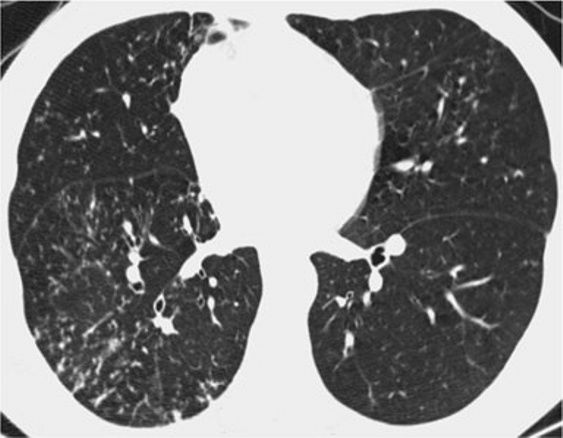

8、囊性病变

囊性模式由界限分明,圆形和外接空气的实质组成,有界限分明的壁和与正常肺。

经典疾病:淋巴管平滑肌肌瘤病(LAM),其特征是通常存在圆形的薄壁肺囊肿,没有在局部明显的特点,分布广泛,包括肋骨角和肺底。 LAM可能伴有胸水表现为胸膜胸腔积液。鉴别诊断是随机分布的囊肿,临床病史表现几乎只影响着育龄妇女。鉴别疾病:是肺组织细胞增生症、淋巴细胞性间质性肺炎(LIP)和小叶性肺气肿。

*LAM。上叶水平的HRCT表现出“囊性模式”,其特征是位于肺实质和隔中的许多大小不等的薄壁“真”囊腔的存在。

肺组织细胞增生症在处于纯囊性期(纯结节性和结节性-囊性期之后的第三期)时模拟LAM。它的特征是存在薄壁和厚壁的囊、形状呈异形,类似于苜蓿叶。囊肿具有特征性以上部和中部肺区分布为主。

*组织细胞增多症。上叶水平的HRCT揭示了一种“囊肿型”,其特征是许多薄或厚的“真”囊肿,形状奇异,大小不一。在右胸膜腔中发现引流导管以治疗气胸,这是这位27岁重度吸烟患者。